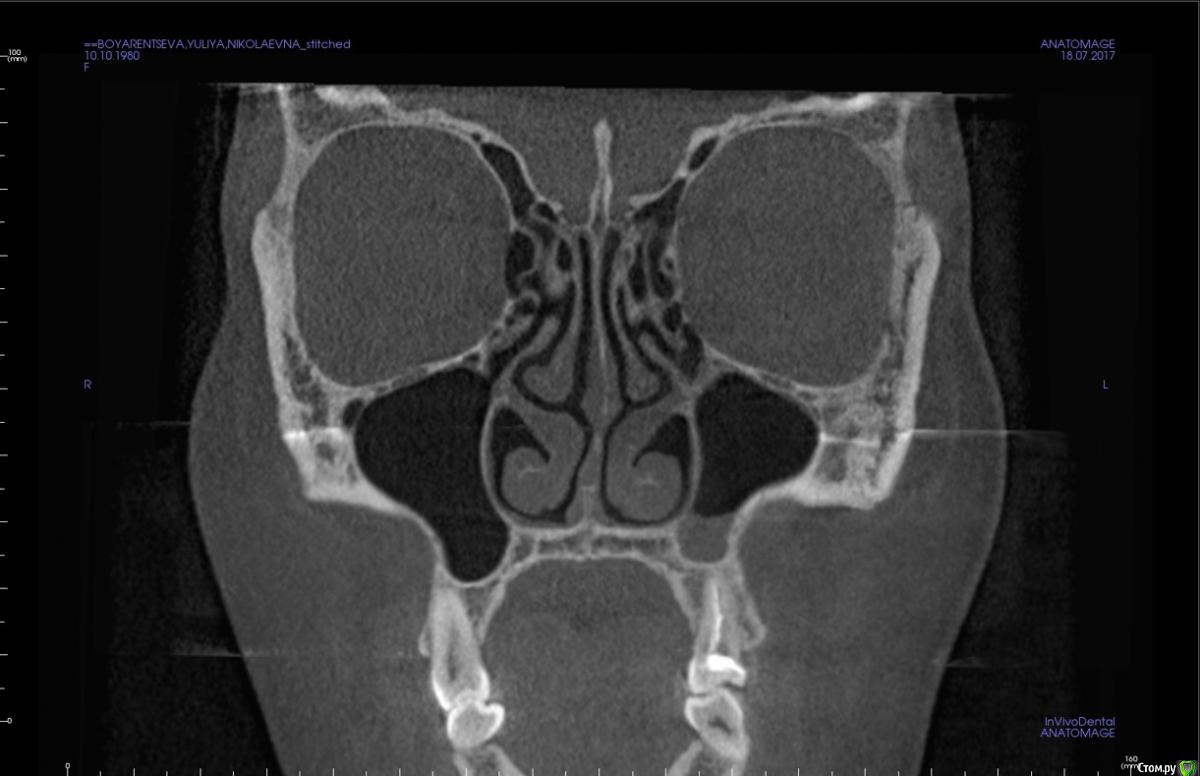

kapyulia Опубликовано 22 декабря, 2017 Поделиться Опубликовано 22 декабря, 2017 Добрый день! Могли бы Вы подсказать есть ли необходимость в удалении зубов (пятерки) с верхней челюсти? Спасибо за помощь. Ссылка на комментарий